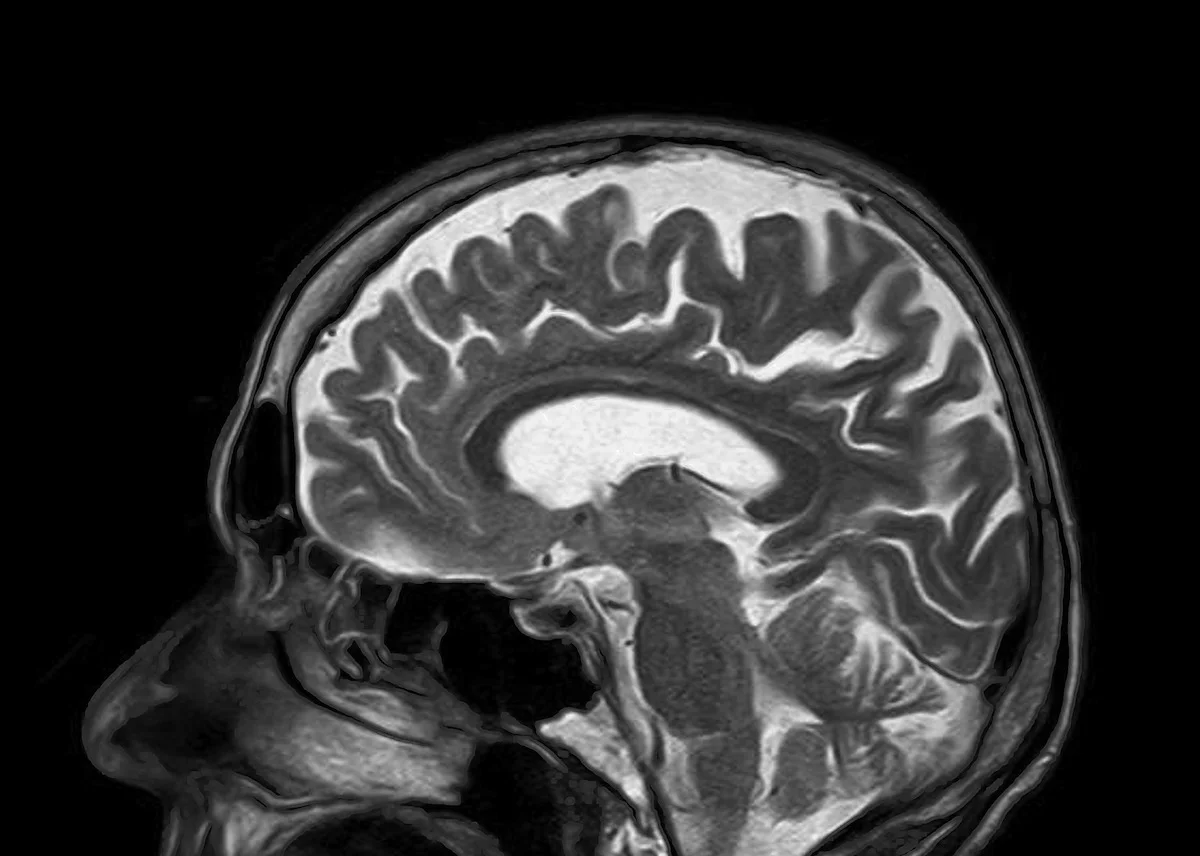

Quantifying mental states and identifying statistical biomarkers of mental disorders from neuroimaging data is an exciting and rapidly growing research area at the intersection of neuroscience and machine learning, with the particular focus on interpretability and reproducibility of learned models. We discussed promises and limitations of machine-learning methods in applications involving fMRI and EEG data; moreover, we summarized some directions related to mental state inference “beyond the scanner,” involving speech and wearable sensors, with applications ranging from clinical settings (“computational psychiatry”) to everyday life (“augmented human”).